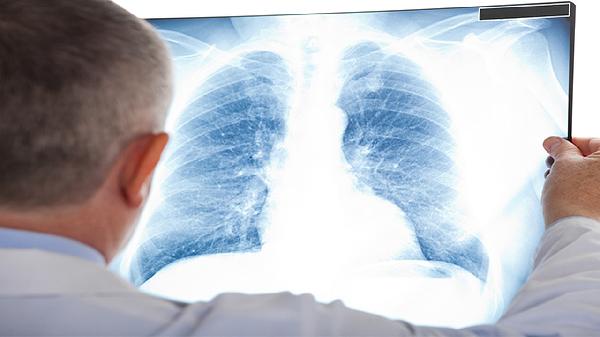

预防肺癌需从日常生活做起,戒烟限酒、避免接触有害物质、保持室内空气流通、适量运动增强免疫力。饮食上多摄入新鲜蔬菜水果,补充维生素和抗氧化物质。出现长期咳嗽、痰中带血、胸痛等症状时应及时就医检查。高危人群建议每年进行一次低剂量螺旋CT筛查,早期发现可显著提高治愈率。